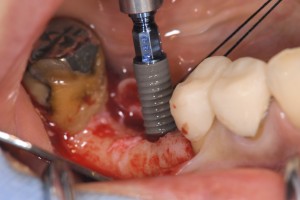

Straumann SLActive Roxlorid親水性サーフェイス埋入中です。

ロキソリッドSLActiveです。

術後の所見です。術後出血もほとんどありません。